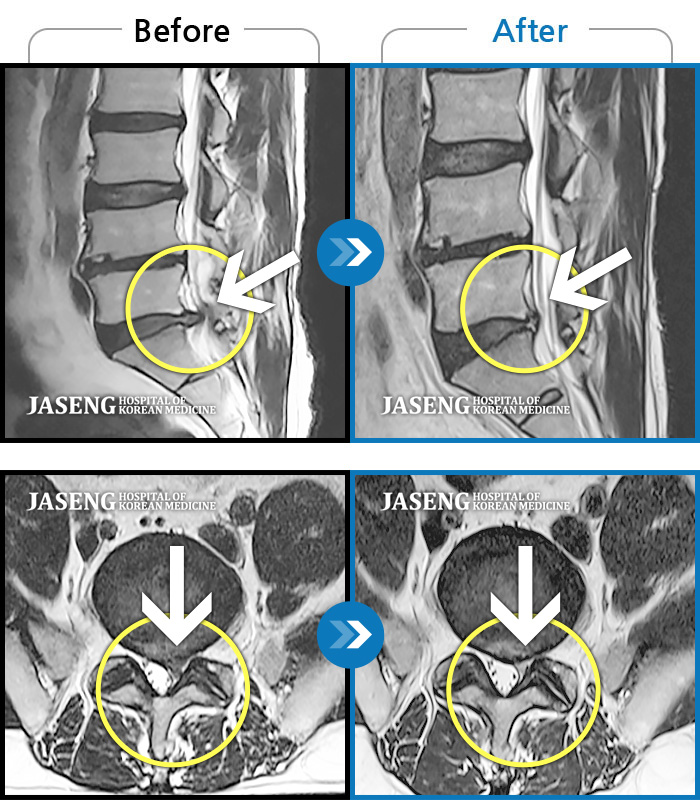

허리디스크

광주 · 김동은 원장

허리부터 골반 및 우측 허벅지에서 발가락까지 묵직한 통증과 저림 발생하여 내원하셨습니다.

촬영시기

2022.07.22 ~ 2025.08.18

2025.08.22